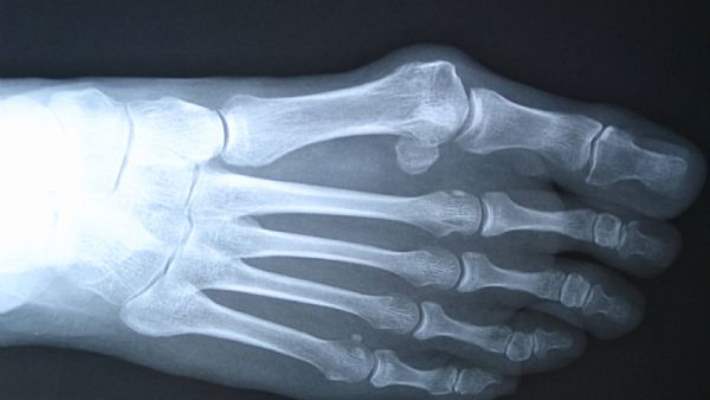

Çoğu zaman Paget hastalığı kalça veya sırt ağrısı şikâyetiyle doktora gidildiğinde teşhis edilir. Kemik röntgeni veya alkalin fosfataz seviyesinin normalden yüksek çıktığı bir kan testiyle hastalık teşhis edilebilir. Tıbbi geçmiş, muayene, kemik röntgeni, laboratuvar testleri ve muhtemelen kemik taraması teşhiste kullanılabilir.Tedavi